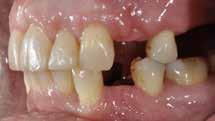

Den kliniske undersøgelse viser harmoniske ekstraorale sagittale forhold med skeletalt dybt bid (Fig. 1A, D). Hendes smil er alderssvarende med en eksponering på 8/10 af overkæbeincisiverne, mens smilets bredde er smalt med synlige mørke laterale rum (Fig. 1D). Underkæbeincisiverne er synlige under tale. Der ses neutrale okklusale forhold ved hjørnetænderne og neutrale pladsforhold i overkæben, men udtalt trangstilling i underkæben især lokaliseret i regio 1-1 (Fig. 1C).

Sliddet klassificeres som grad 2 (moderat tandslid) på de centrale incisiver i overkæbe og underkæbe. Det kan anses som patologisk, da det er atypisk for patientens alder, giver anledning til smerte/ubehag, og giver patienten et æstetisk problem. Der ses infraktioner af overkæbeincisiverne. Der ses endvidere en udtalt Spee-kurve i underkæben og ingen interincisal afstøtning på 2-2 med let ganepåbidning.

Røntgenanalyse viser fravær af -6 samt et velholdt tandsæt uden tegn på sygdom. Profilrøntgenbilledet viser et skeletalt

dybt bid, men normal inklination af fortænder i over- og underkæbe (Fig. 1B).